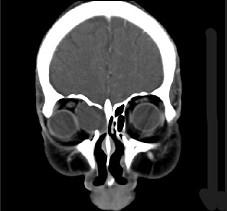

问题 女性,38岁,右侧眼球运动障碍伴眼球突出4个多月,CT扫描如图,请选择正确的描述和答案 ( )

选项 A、考虑为右侧筛窦黏液囊肿 B、考虑为筛窦癌 C、囊性肿块向右侧眼眶内突入,压迫内直肌 D、右侧眶内壁呈受压变薄、断裂 E、右侧筛窦内可见囊性肿块影,边缘光整

答案 ACDE